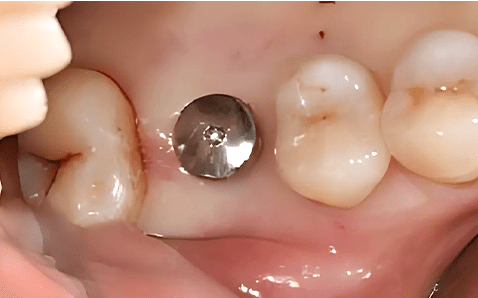

Case 01

Before Implant Placement Right After Flapless Implant Placement

Photo Date : 2024.12.05